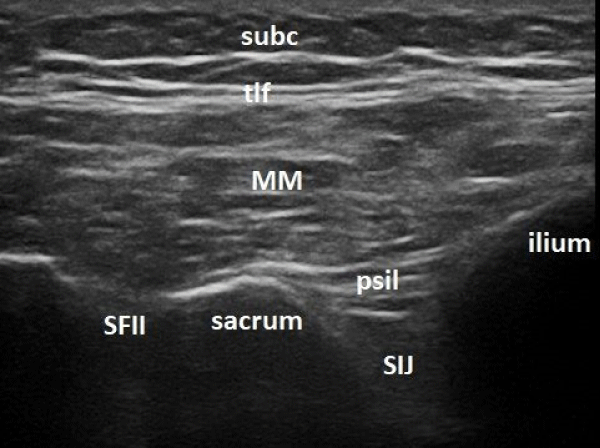

Figure 2:

Ultrasound image of the sacroiliac joint with the transducer positioned as in figure 2 (SIJ – sacroiliac joint; SFII – second sacral foramen; psil – posterior sacroiliac ligament; MM -multifidus muscle; tlf -thoracolumbar fascia; subc – subcutaneous tissue).